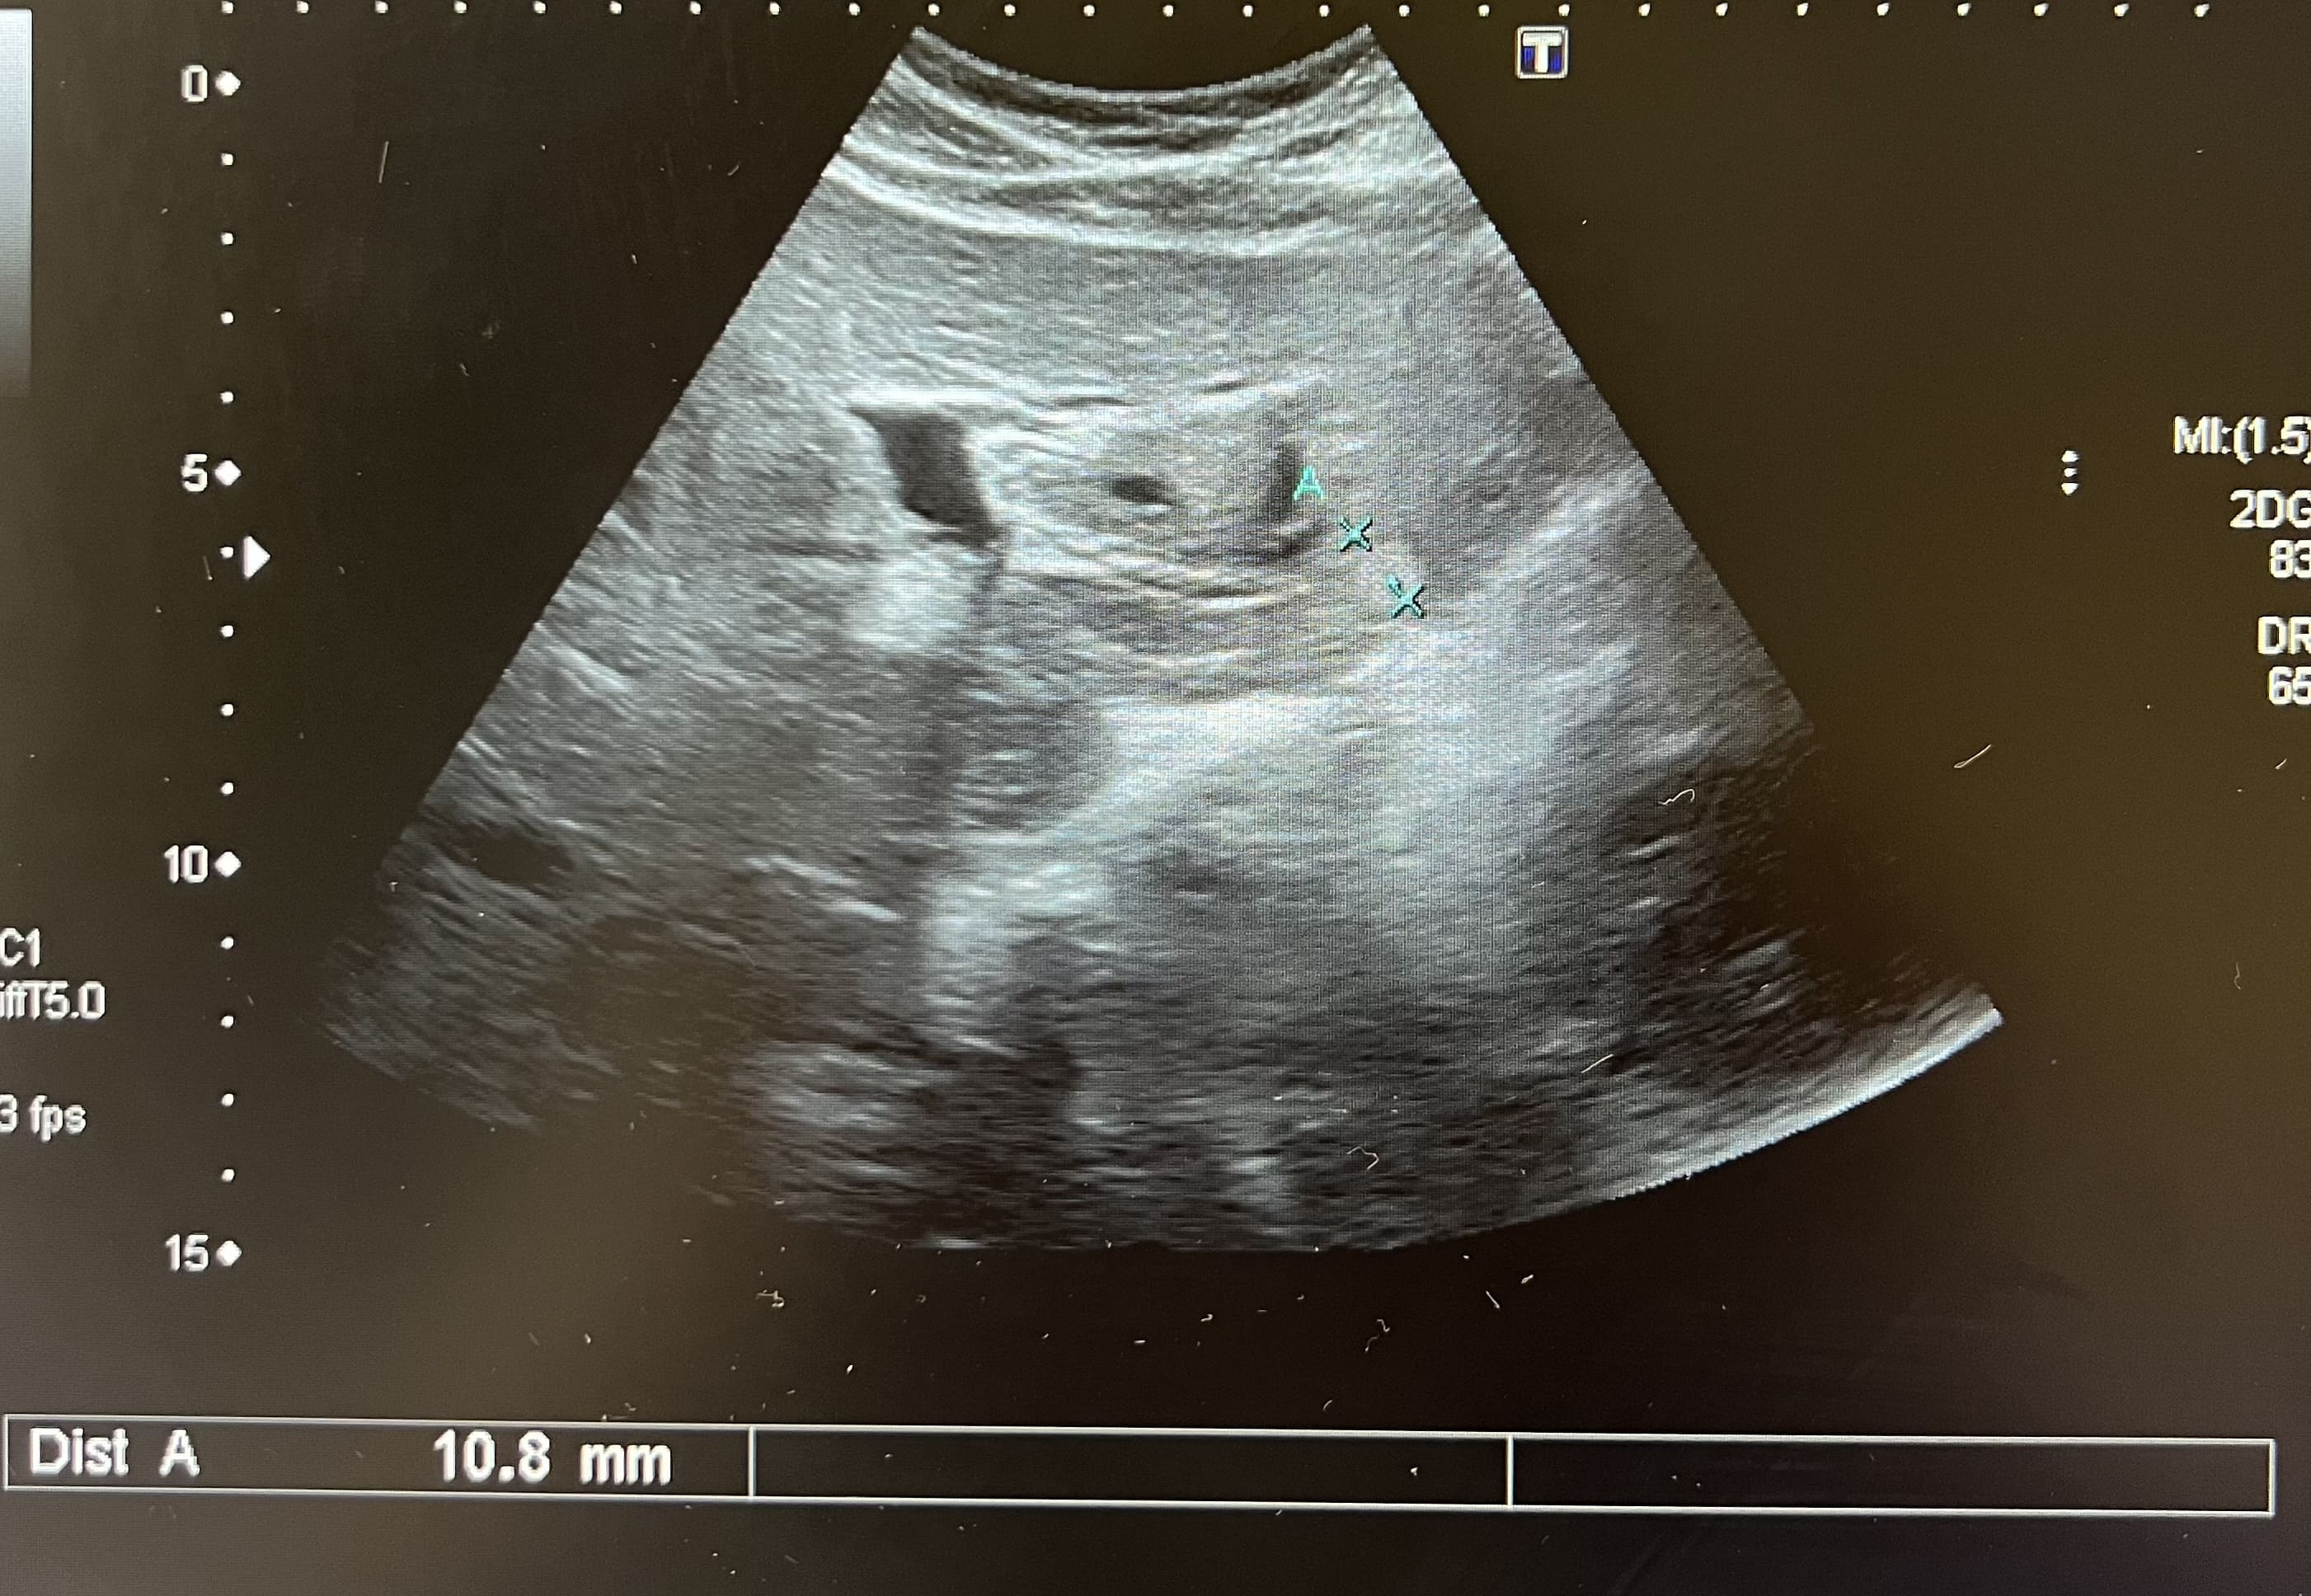

Pruebas complementarias: analítica normal. La ecografía abdominal muestra múltiples imágenes ecogénicas bien definidas en ambos lóbulos, de tamaño variable. Vesícula biliar con dos litiasis subcentimétricas y discreto edema de pared compatible con colecistitis. Estos hallazgos se confirman mediante la realización de una ecografía reglada por parte de radiología.

Juicio clínico: Hemangiomas hepáticos. Colecistitis.

Diagnóstico diferencial: con otras lesiones focales sólidas del hígado. La imagen ecográfica del hemangioma es de una o varias lesiones hiperecogénicas bien definidas que no captan Doppler. La hiperplasia nodular focal se presenta como una lesión hipo o isoecoica que puede captar Doppler. El adenoma se presenta como una masa hiper o hipoecoica con áreas anecoicas, mostrando el Doppler un tumor hipervascular. El hepatocarcinoma tiene un aspecto ecográfico variable, como masa o nódulos hipoecoicos, mal diferenciados e hipervascularizados. Las metástasis hepáticas se suelen presentar como múltiples lesiones sólidas de tamaño y ecogenicidad variables y la presencia de un halo hipoecoico rodeando la masa.

El hemangioma hepático es el tumor hepático benigno más frecuente, con mayor prevalencia en mujeres. Se suelen presentar en forma de lesión única, aunque pueden aparecer en forma de lesiones múltiples, con un tamaño normalmente inferior a 30 milímetros. Suele ser un hallazgo casual, al ser asintomáticos. El diagnóstico diferencial se realiza con otras lesiones hepáticas sólidas y se recomienda un seguimiento ecográfico para confirmar estabilidad.